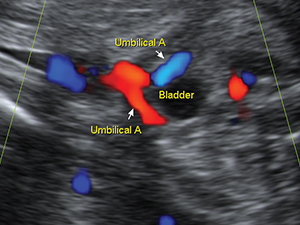

腹部

胎兒膀胱